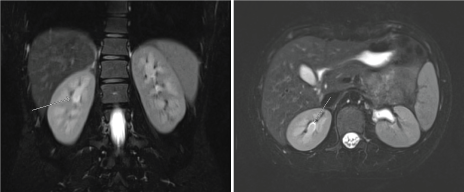

The patient underwent cystoscopy with bilateral retrograde pyelogram that revealed efflux of bloody urine from the left ureteral orifice, and filling defects in the left renal pelvic and lower pole calyx (Figure 1). The ureter was stented with a double J stent and subsequent ureteroscopy was performed. The patient was found to have renal papillae which were significantly hypertrophied and highly vascularized (Figure 2). The papilla of the lower pole calyx was hypertrophic to the point of protrusion into the renal pelvis. These hypertrophied lesions were biopsied and then ablated with a holmium laser. Pathology revealed benign fragments of renal medulla with tubular calcifications. MR angiogram performed one month later showed no vascular lesions or malformations. MR urogram showed prominent medullary pyramids in bilateral upper poles, consistent with renal papillary hypertrophy (Figure 3). The patient was followed without recurrence of hematuria for over 9 months.

Figure 3: MR Urogram showing prominent bilateral upper pole medullary pyramids consistent with papillary hypertrophy. Case 1-EC. View Figure 3